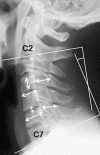

Methods: A total of 1,230 asymptomatic volunteers underwent anteroposterior (AP), lateral, flexion, and extension radiography of the cervical spine. There were at least 100 men and 100 women in each decade of life between the 3rd and 8th. AP diameter of the spinal canal, vertebral body, and disc were measured at each level from the 2nd to 7th cervical vertebra (C2-C7). C2-C7 sagittal alignment and ROM during flexion and extension were calculated using a computer digitizer.

Results: The AP diameter of the spinal canal was 15.8 ± 1.5 [mean ± standard deviation (SD)] mm at the mid-C5 level, and 15.5 ± 2.0 mm at the C5/6 disc level. The disc height was 5.8 ± 1.3 mm at the C5/6 level, which was the minimum height, and the maximum height was at the C6/7 level. Both the AP diameter of the spinal canal and disc height decreased gradually with increasing age. The C2-C7 sagittal alignment and total ROM were 13.9 ± 12.3° in lordosis and 55.3 ± 16.0°, respectively. The C2-C7 lordotic angle was 8.0 ± 11.8° in the 3rd decade and increased to 19.7 ± 11.3 in the 8th decade, whereas the C2-C7 ROM was 67.7 ± 17.0° in the 3rd decade and decreased to 45.0 ± 12.5 in the 8th decade. The extension ROM decreased more than the flexion ROM, and lordotic alignment progressed with increasing age. There was a significant difference in C2-C7 alignment and ROM between men and women.